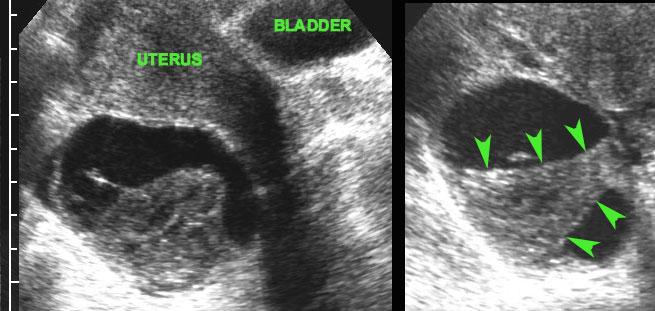

Ca lâm sàng 2

Ở người phụ nữ trẻ này với hai ngày đau hố chậu phải và CRP bằng 2, siêu âm phát hiện một nang buồng trứng bên phải thành mỏng.

Siêu âm đầu dò âm đạo (TVUS) cho thấy hình ảnh điển hình của các vách ngăn mỏng như ren, đồng thời thấy phần buồng trứng bình thường còn lại chứa các nang noãn bị “đẩy” sang một bên bởi nang xuất huyết.

Hình ảnh hoàn toàn bình thường sau 6 tuần.